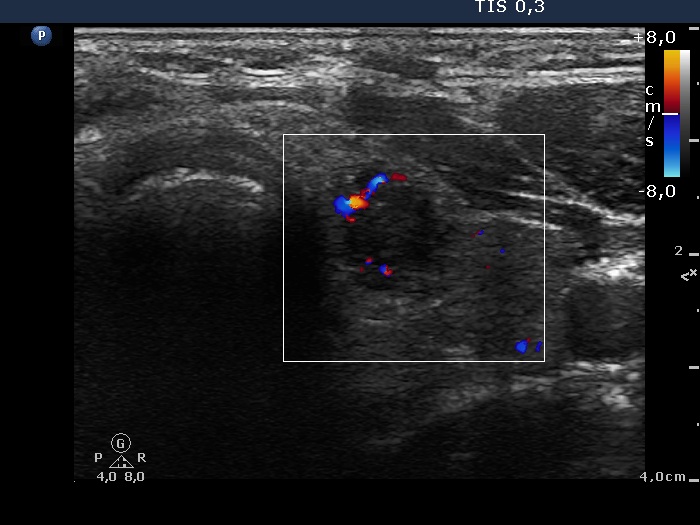

Left lobe, transverse scan, color Doppler mode. The vascularization is not specific.